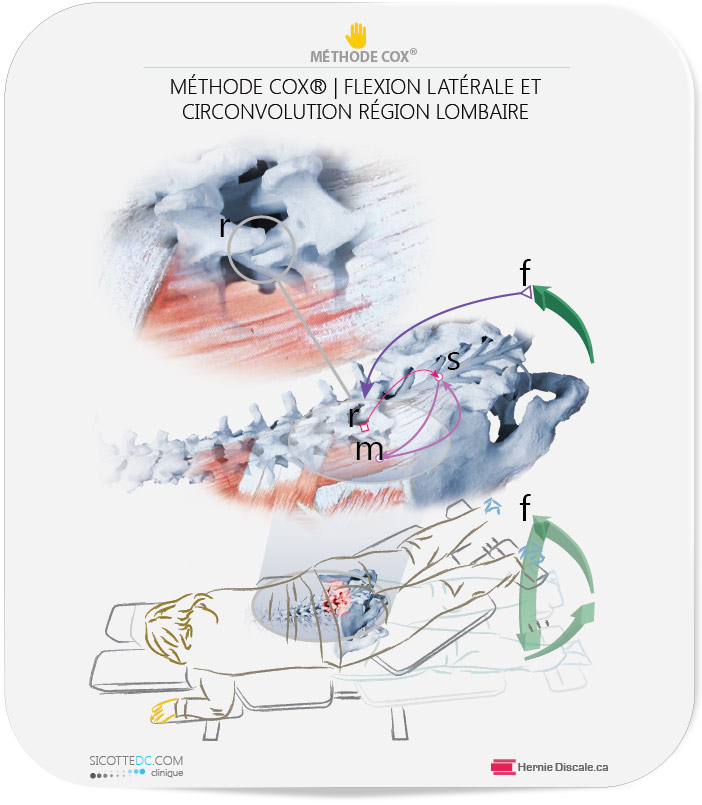

COMMENT LE TRAITEMENT NATUREL COX® AIDE À DIMINUER LES EFFETS NÉFASTES DE L’ARTHROSE LOMBAIRE

L’objectif est de mobiliser les segments où se trouve la discarthrose (discopathie) vertébrale.

COMMENT FONCTIONNE UN TRAITEMENT COX®